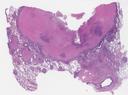

病理切片

SLIDE